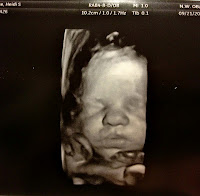

I am 35 weeks along now, and we are really getting excited about meeting Noa~ wondering what her personality will be like, her eye and hair color...all those normal exciting things a parent wonders! We will see. I look forward to watching the other kids (especially Ruby) welcome her into the family. I suspect Ruby will try to help with Noa and love her alot.

| Tiny toes on her forehead |

| 35 Weeks and counting |